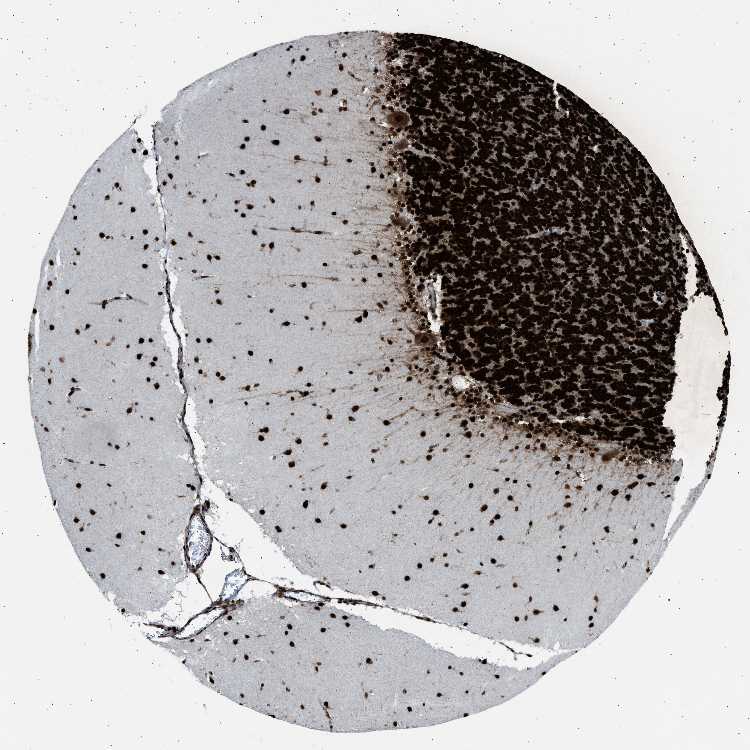

BRAIN CEREBELLUM Show tissue menu

CEREBELLUM - Expression summary

CEREBELLUM - Antibody stainingi

Antibody staining in the annotated cell types in the current human tissue is reported as not detected, low, medium, or high, based on conventional immunohistochemistry profiling in selected tissues. This score is based on the combination of the staining intensity and fraction of stained cells.

Each image is clickable and will lead to virtual microscopy that enables deeper exploration of all samples and also displays staining intensity scores, fraction scores and subcellular localization as well as patient and tissue information for each sample.

Antibody HPA007644Antibody CAB004435Antibody CAB016225

Purkinje cells LowHighHigh

Cells in granular layer HighHighHigh

Cells in molecular layer HighHighHigh